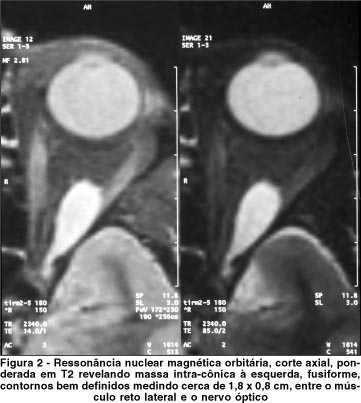

A tomografia computadorizada orbitária e a ressonância nuclear magnética mostraram massa intra-cônica à esquerda, fusiforme, de contornos bem definidos, medindo cerca de 1,8 x 0,8 cm, localizada entre o nervo óptico e o músculo reto lateral esquerdo, borrando os contornos desse músculo (Figura 1 e 2).